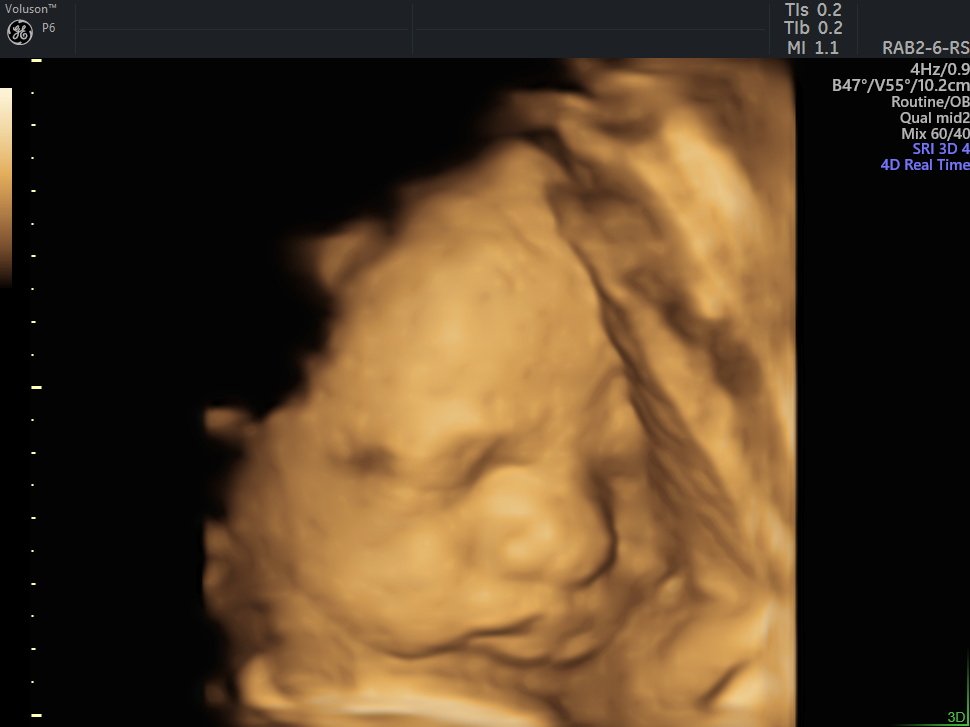

4 D Ultrasonografi

4 Boyutlu (Renkli) Ultrason ve Doppler Ultrasonografi